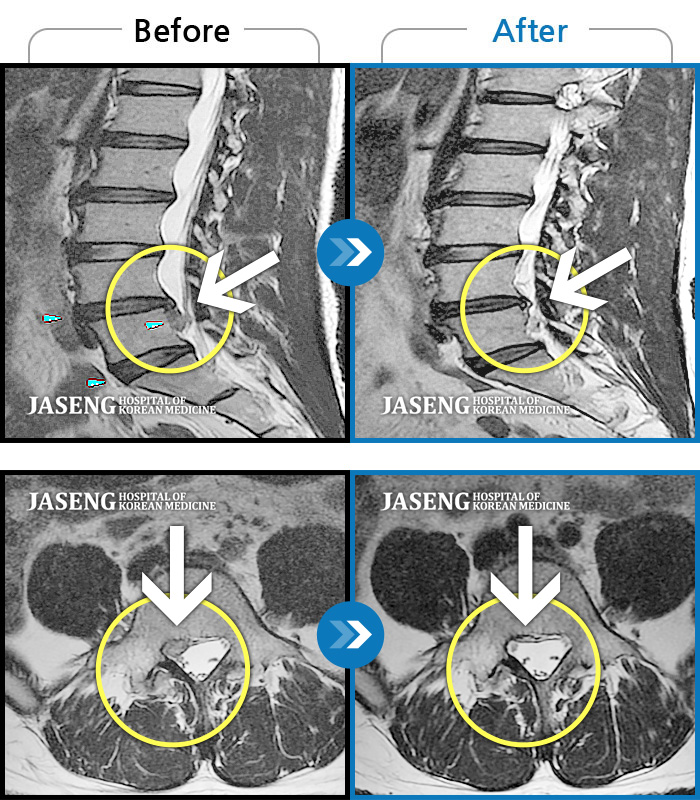

허리디스크

보라매 · 빈상은 원장

엉치에서 좌측 다리 뒤쪽으로 통증과 저림이 매우 심해요.

촬영시기

2024.06.08 ~ 2024.08.31

2024.12.24

조회수 461